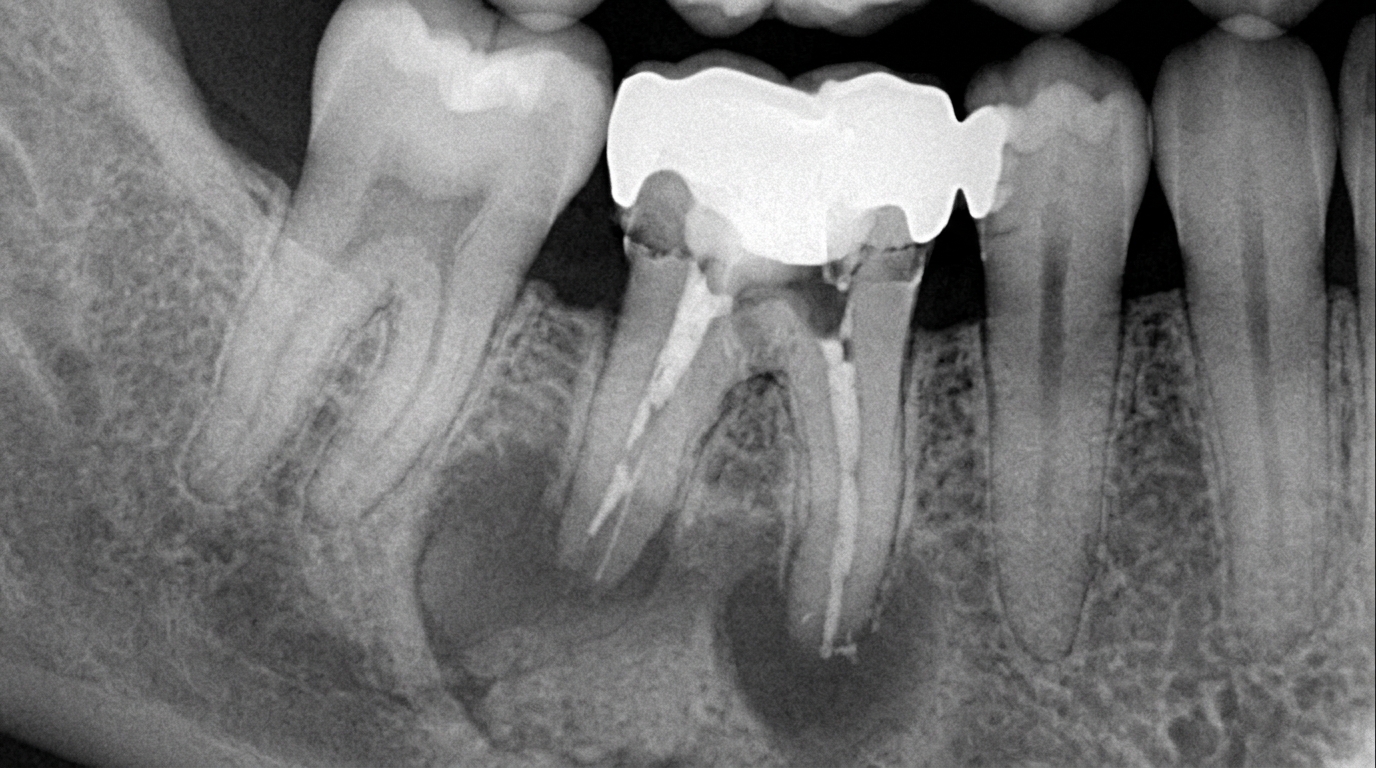

Рентгеновский снимок зуба с коронкой, иллюстрирующий возможные причины запаха: скопление бактерий под конструкцией.

В кабинете стоматолога диагностика начинается с визуального осмотра и пальпации. Врач использует увеличительную оптику для выявления микротрещин или дефектов фиксации. Рентгенография — ключевой этап: панорамный снимок или КТ покажет состояние корня, наличие гранулемы или перелома. В 2026 году популярны цифровые рентгены с ИИ-анализом в клиниках Евродент и32plus, где доза облучения минимальна, а результат готов за минуты.

Процесс диагностики: рентген, лазерная чистка и переполировка коронки на месте.